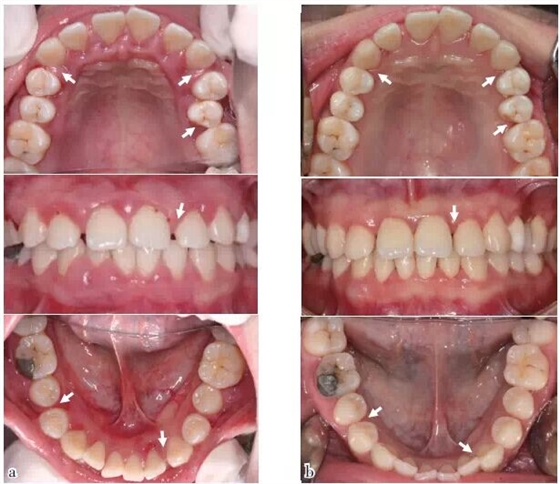

圖1 口內(nèi)照:與初診相比,SRP及咬合干預后,牙齦炎癥減輕,25排列整齊,多處牙間隙變小或關閉(箭頭),(a)2011/12初診,(b)2014/11評估